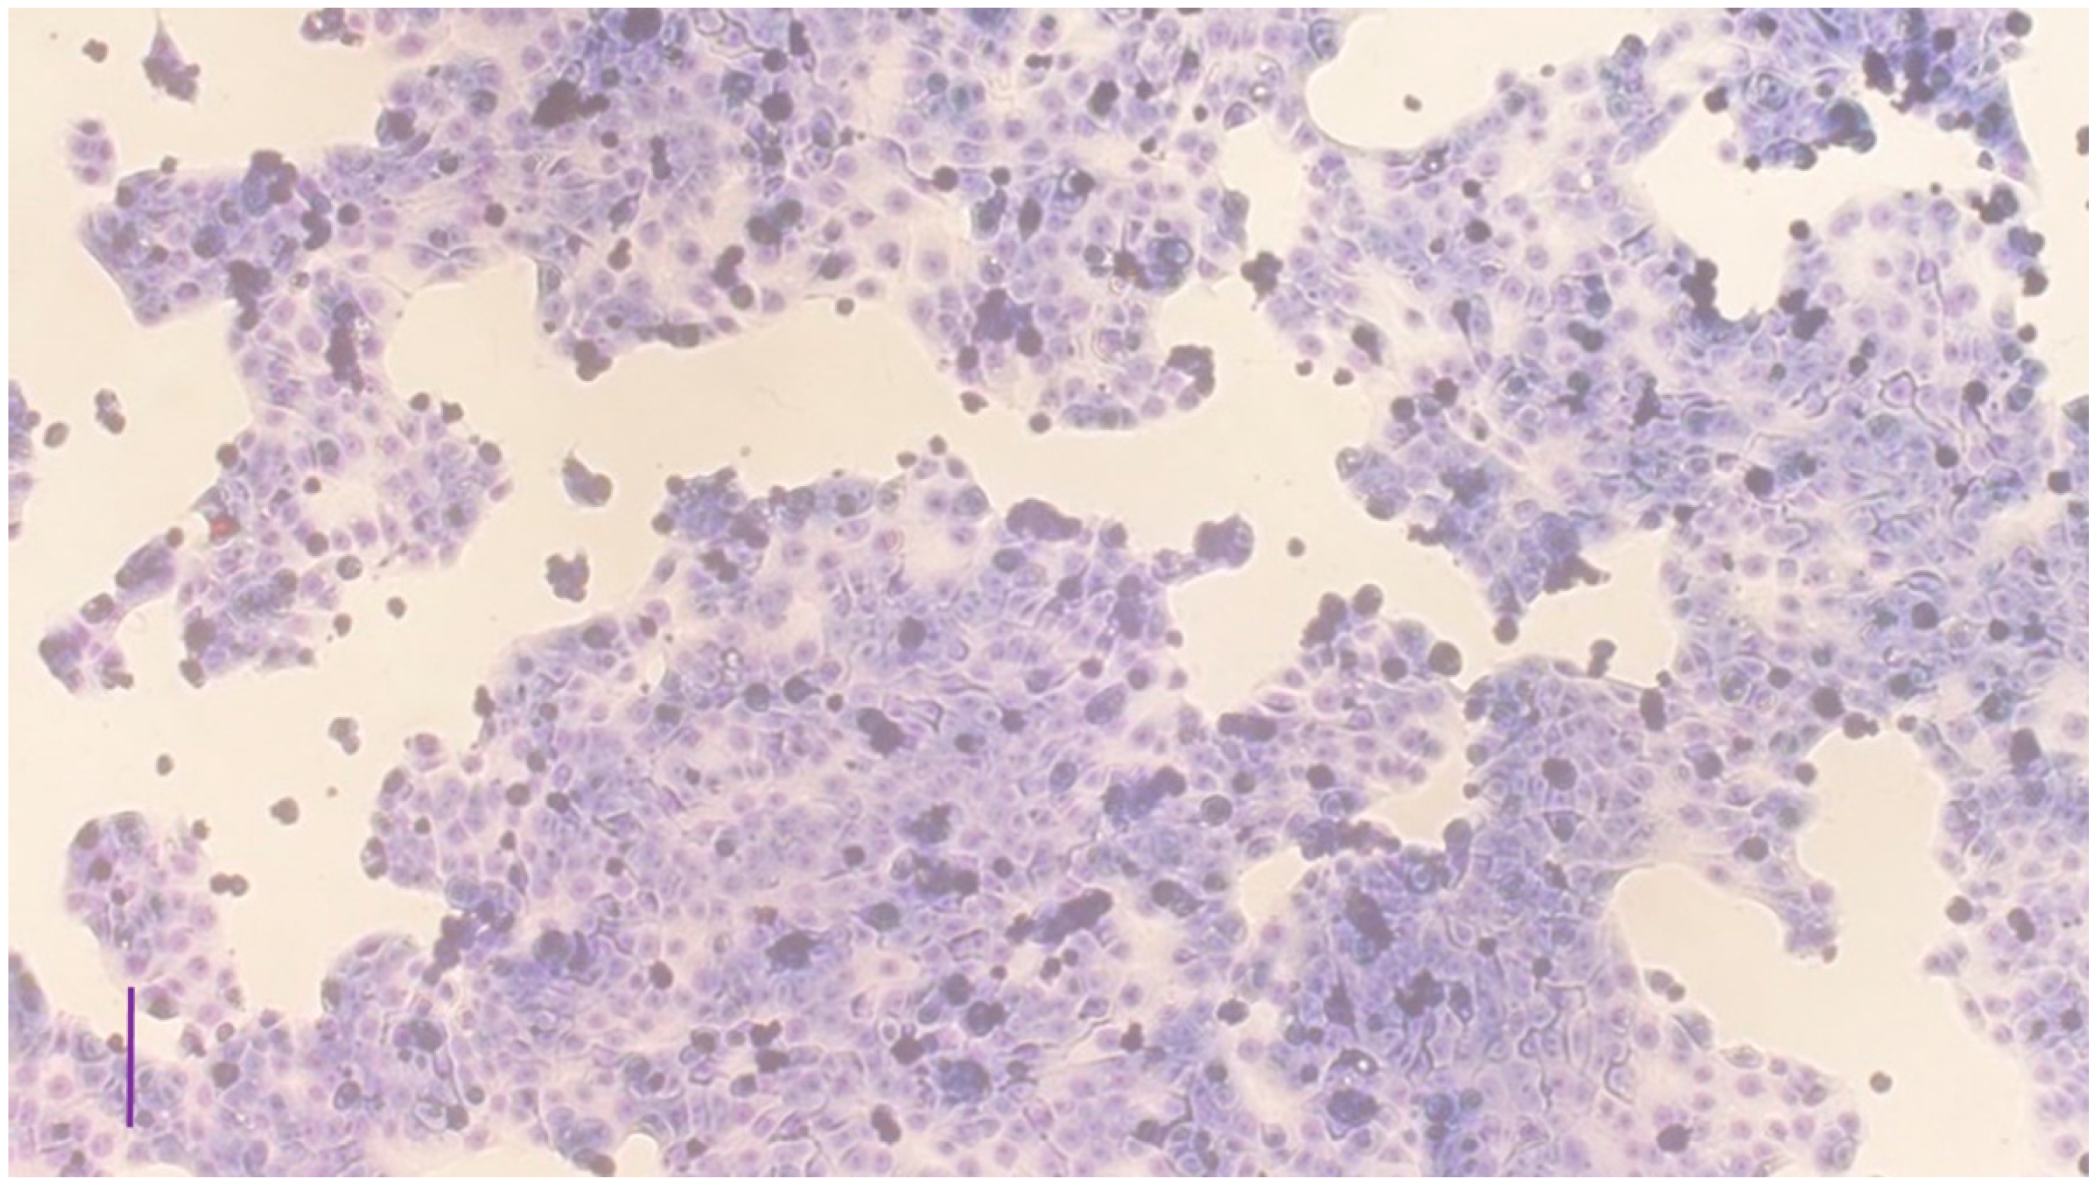

2.3. Characterization of the Cell Culture

3.1. Characterization of the Cell Cultures